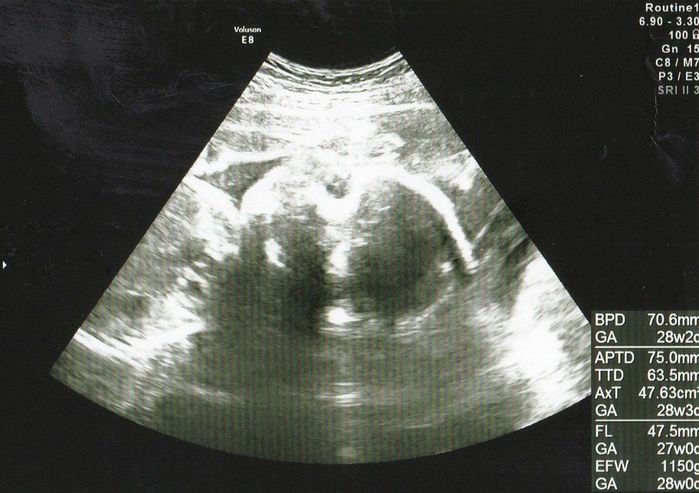

妊娠26週目のエコー写真 画像におさまりきらないわが子の成長に感動

推定体重=1150g

お顔を反対側に向けた頭部のエコー画像です。体は左側にあります。赤ちゃんの体重が1kgを超え、私のおなかも妊婦らしくなってきました。エコーでは赤ちゃんの体全部が入らなくなり、大きくなったことを実感しました。診察の際には、足をのばして、のびのびしている姿を見ることができておもしろかったです。私の体調は安定しており、法事のため新幹線で出かけたり、仕事も忙しかったり、妊娠前のようにバタバタと過ごしていました。